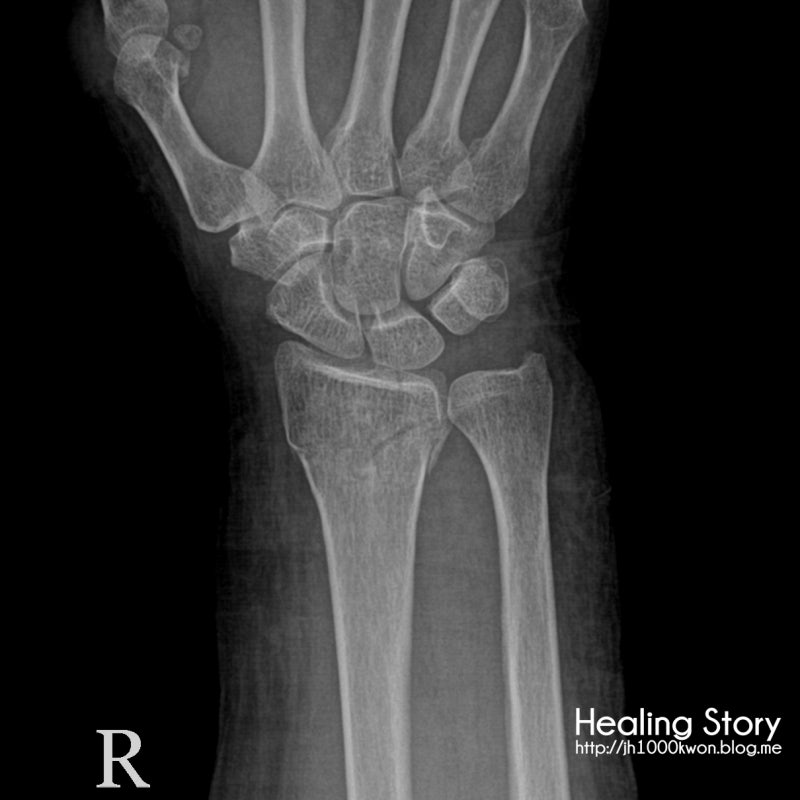

(손뼈) 6-5. 손목 뼈 (바디 해커 나탕)

오른쪽 손목 뼈의 손바닥 보기

수근골은 2줄(8조각)로 배열되어 있으며 각 손에 4조각씩 있습니다. 왼쪽 이미지는 근위 수근골(요골/척측)을 보여주고 오른쪽 이미지는 원위 수근골(중수골 쪽)을 보여줍니다. 수근골 사이의 관절 수근골은 편평하거나 쐐기 모양으로 인대에 의해 연결되어 있지만 움직임이 거의 없어 손목 관절이나 손 부착 부분의 굽힘 운동을 형성합니다. 엄지손가락 옆에서 새끼손가락까지(바깥쪽에서 안쪽으로) 두상골. 근위 수근골 중 손의 뼈와 몸 옆면의 반월상연골이 손목 관절(radius)과 만나 손목 관절(radius)을 형성합니다. 원위 수근골은 또한 큰 사다리꼴, 작은 사다리꼴 및 머리뼈로 구성됩니다. , 그리고 엄지손가락 옆에서 새끼손가락까지의 햄테. 원위 수근골은 5개의 중수골과 연결되어 수근중수관절을 형성하고 중수골과 능형골 양쪽에 결절이 있다. 새끼손가락 쪽 유구의 손바닥 표면에 유구(손바닥 다발과 함께 튀어나와 손바닥 양 옆을 들어올림)가 있고 척골 쪽 유구와 유구 사이에 홈이 있다. , 이 곳을 수근골(carpal groove)이라고 하며 굴근지지대(flexor support band)는 고랑의 양쪽 끝 뼈에 부착되어 등이 통과하는 터널을 형성한다.